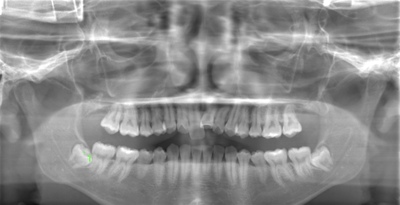

CASE 17

| 年齢・性別 | 18歳・男性 |

| 主訴 | 矯正を開始する前に左下と左上の親知らずを抜きたい |

| 抜歯期間 | 約1時間 |

| 抜歯費用 | 1本22,000円×2本 合計44,000円 (2022年10月現在) |

| 抜歯内容 | 完全埋伏抜歯 |